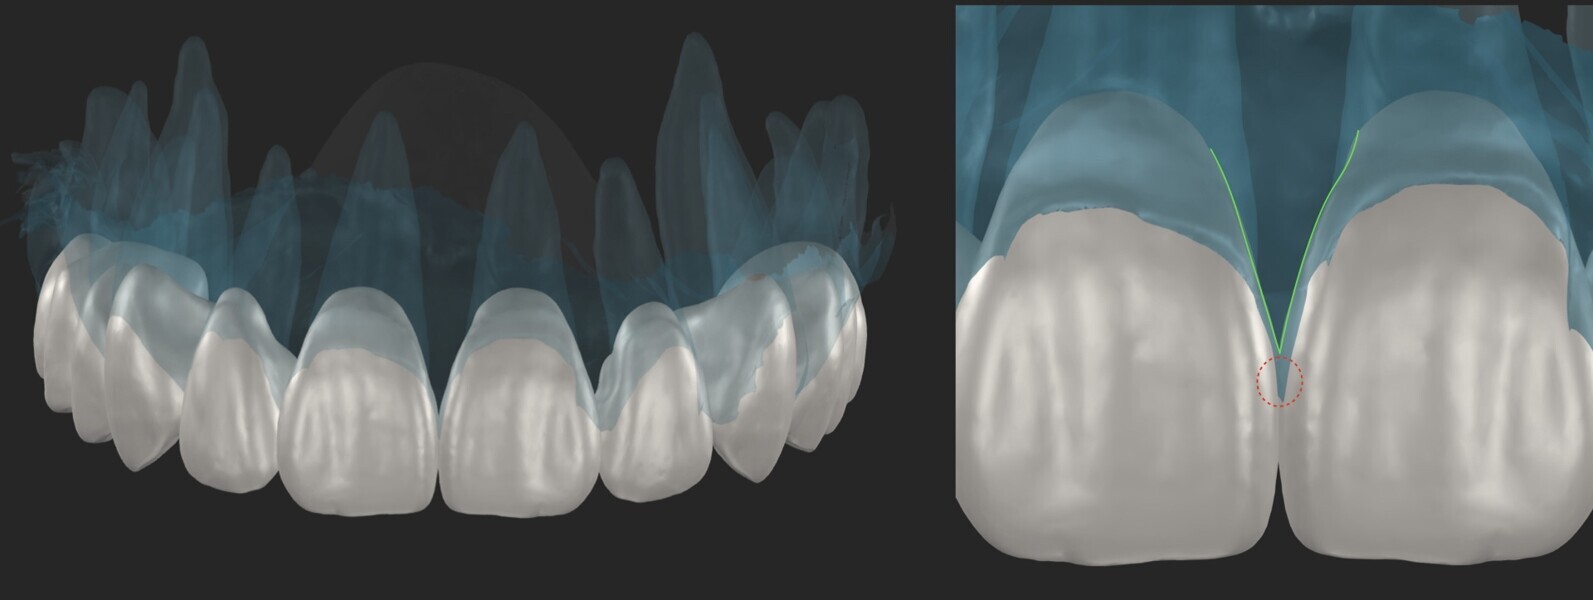

We begin with facial analysis and use planning software to select the appropriate tooth forms that complement the patient’s facial structure and determine the optimal apico-coronal tooth positioning. This step is particularly beneficial when the software allows us to modify tooth forms in relation to the patient’s soft-tissue contours, including papillary height, ideal gingival zeniths and other critical aesthetic parameters (Fig. 5). For this patient, as we aimed to achieve high papillae and have an excess of soft tissue to manipulate, we opted for trapezoidal tooth forms or potentially triangular forms rather than square ones. Once the desired tooth forms are selected, they are exported to a 3D CAD software program for precise positioning in the buccolingual dimension.

In this specific case, we strategically positioned the design palatally and more coronally. This compensated for the existing occlusal disharmonies while also shaping the soft tissue for prosthetically guided healing of the extraction sites. By integrating these adjustments, we could harmonise the patient’s bite and smile, achieving both function and aesthetics (Figs. 8–10).